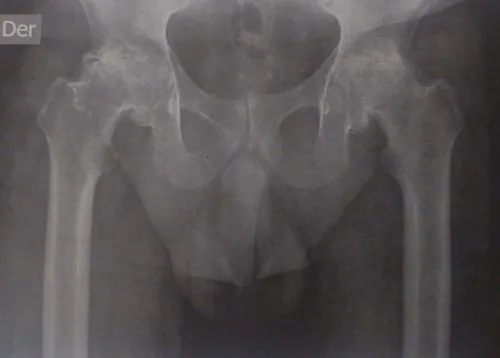

Preoperatorio

Artroplastia bilateral simultánea con utilización de tallo femoral acortado (short stem). Esta opción preserva mayor stock óseo y facilita una fijación biológica óptima. Alta a las 24 horas caminando con andador.